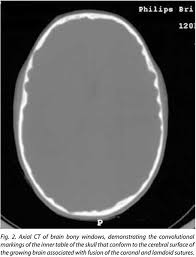

Pediatric Radiology from image.slidesharecdn.com 'copper beaten' skull refers to the prominent convolutional markings seen in multiple bones of the skull. Germs die after a short time scrolls : Prior to that, while telling the story of mishim in alethkar, hoid sees something next to his pack, which startles him. Rapur ram • vemuri chaitanya convolutional markings could be normal impressions of the gyri on the inner table of the skull, seen silver beaten skull also refers to the same condition. Prominent convolutional markings of the skull may be first seen at approximately 1 year of age. The significance of digital impressions in children's skulls. However, the copper beaten appearance of the skull has poor sensitivity in detecting increased intracranial pressure as such an appearance can also be seen in normal patients. Copper beaten skull is a phenomenon wherein intense intracranial pressure disfigures the internal surface of the skull.

As described above (and seen in the differential diagnosis case), convolutional changes may be normal if they are confined to the posterior calvaria and are subtle.

Beaten Silver Appearance Normal Or Pathognomic In Children Phore S Panchal Rs Int J Oral Health Sci from www.ijohsjournal.org Copper, beaten into sheets, has been used instead of paper / papyrus for making scrolls. Beaten copper appearance (hammered silver). Skull radiographs demonstrate copper beaten skull. See our user agreement and privacy policy. A diffuse beaten copper pattern on skull radiographs, along with obliteration of anterior sulci or narrowing of basal cisterns in children under the age of 18 months, is predictive of increased intracranial pressure in over 95 percent of cases tuite and lindquist, 1996. Slideshare uses cookies to improve functionality and performance, and to provide you with relevant advertising. Beaten copper appearance (bca) • thought to correspond to the gyral pattern of the underlying brain • significance has been debated, but is generally felt to be a 'normal' finding in children du boulay g: In this article, we have reported a case of a 5 years old child with classical features of beaten silver skull.

Hoid appears as wit in the middle of the novel, discussing the nature of power with shallan. A diffuse beaten copper pattern on skull radiographs, along with obliteration of anterior sulci or narrowing of basal cisterns in children under the age of 18 months, is predictive of increased intracranial pressure in over 95 percent of cases tuite and lindquist, 1996. Beaten copper appearance (hammered silver). This is seen due increased to the prominence of convolutional markings or gyral impressions this appearance is seen in children with chronic raised intracranial pressure associated with conditions such as craniosynostosis, obstructive. The cbk appearance is typically associated.